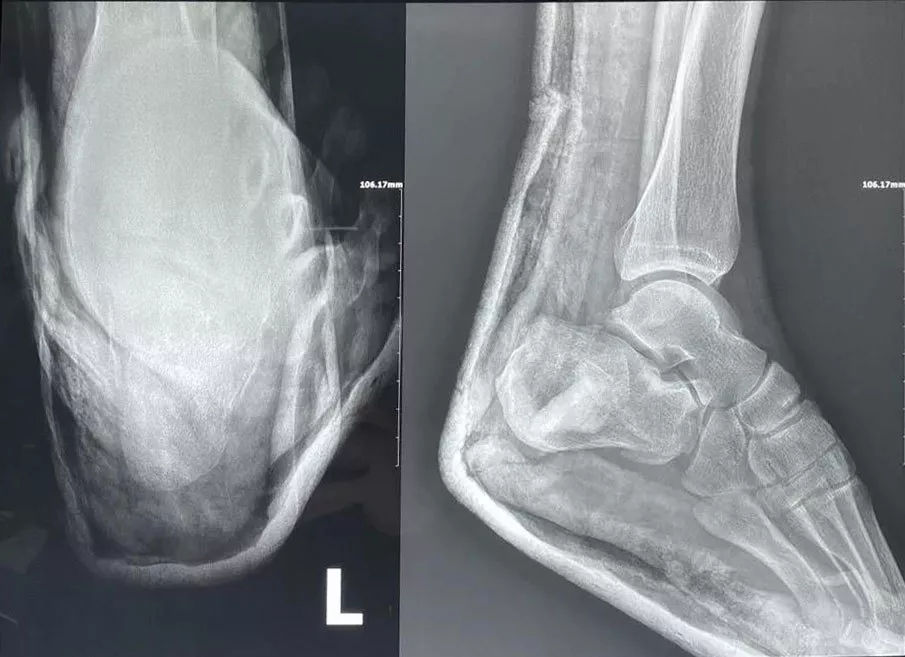

手術(shù)中透視跟骨骨折解剖復(fù)位

而跟骨骨折的微創(chuàng)治療——跗骨竇切口,只需要在足跟部作兩個(gè)微創(chuàng)小切口,通過解剖復(fù)位跟骨關(guān)節(jié)面,恢復(fù)跟骨的長(zhǎng)度和高度,避免后期出現(xiàn)創(chuàng)傷性關(guān)節(jié)炎和跟腓撞擊癥,同時(shí)能有效的避免手術(shù)切口的皮膚壞死和切口感染。